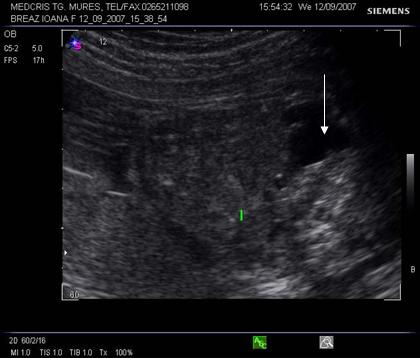

Fig. nr. 271. Formatiune abdominala fetala , la o sarcina de 34 sapt, sex feminin, sugestiva pentru un teratom ovarian.

Fig. nr. 272.

Acelasi fat din figura precedenta, se remarca formatiunea anecogena

intraabdominala, bine delimitata, ce contine o zona ecogena, sugestiva pentru

un teratom. Cu sageata , vezica urinara.